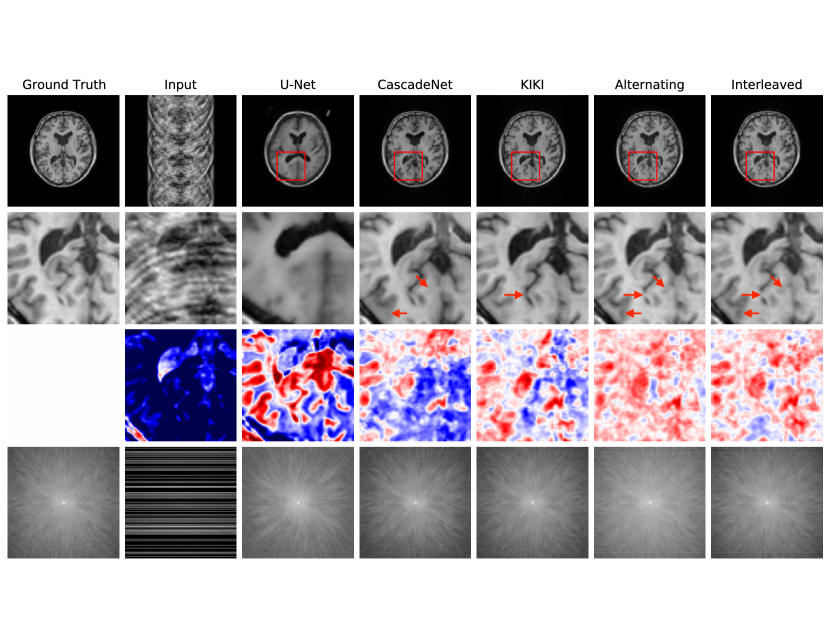

Fig. 4 reports reconstruction quality statistics for all four types of simulations described in Section 4.1.1: motion, noise, undersampling, and motion combined with undersampling. The Interleaved and Alternating architectures outperform the baseline architectures for nearly every task and subject. Across all tasks and nearly all subjects, the Interleaved and Alternating architectures are quite similar in numerical performance. Sample image reconstructions for the motion, motion with undersampling and denoising tasks are shown in Figs. 5-7. Qualitatively, for each task, the Frequency network provides a blurry version of the ground truth image. The Image network provides a reconstruction which effectively removes ‘background’ effects but has limited success in correcting these artifacts within the image. In contrast, the Interleaved and Alternating networks provide sharper, high-quality reconstructions across all tasks. Further, the frequency space reconstructions provided by those networks appear the most faithful to the ground truth frequency data.

We compare Interleaved and Alternating networks to a U-Net (Falk et al., 2019), the CascadeNet (Schlemper et al., 2017), which combines image space convolutions with forced data consistency at each layer of the network, and, most similar to our method, the KIKI network (Eo et al., 2018), which includes two separate image and frequency space networks. The KIKI-net architecture incorporates four networks operating in the frequency, image, frequency, and image spaces, respectively. This is in contrast to our networks, where every layer contains convolutions in both spaces and uses a custom nonlinearity for the frequency space layers. Moreover, the KIKI-net architecture imposes a data consistency constraint after each k-space subnetwork. For tasks other than undersampled image reconstruction, the data consistency constraints in CascadeNet and KIKI-net would incorrectly force the acquired k-space lines to be maintained in the final reconstruction; thus, we restrict comparisons with CascadeNet and KIKI-net to the undersampled reconstruction case.

4.2.1 Results

Fig. 8 reports statistics for U-Net, CascadeNet, KIKI-net, Joint and Alternating networks. Fig. 9 provides sample image reconstructions. Interleaved and Alternating networks perform comparably to other state of the art methods on the simpler uniform undersampling tasks and outperform the state of the art methods on the more complex random undersampling task.